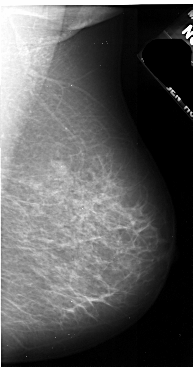

A_1036_1.LEFT_MLO

LEFT_MLO LINES 5251 PIXELS_PER_LINE 2641 BITS_PER_PIXEL 16 RESOLUTION 42 OVERLAY